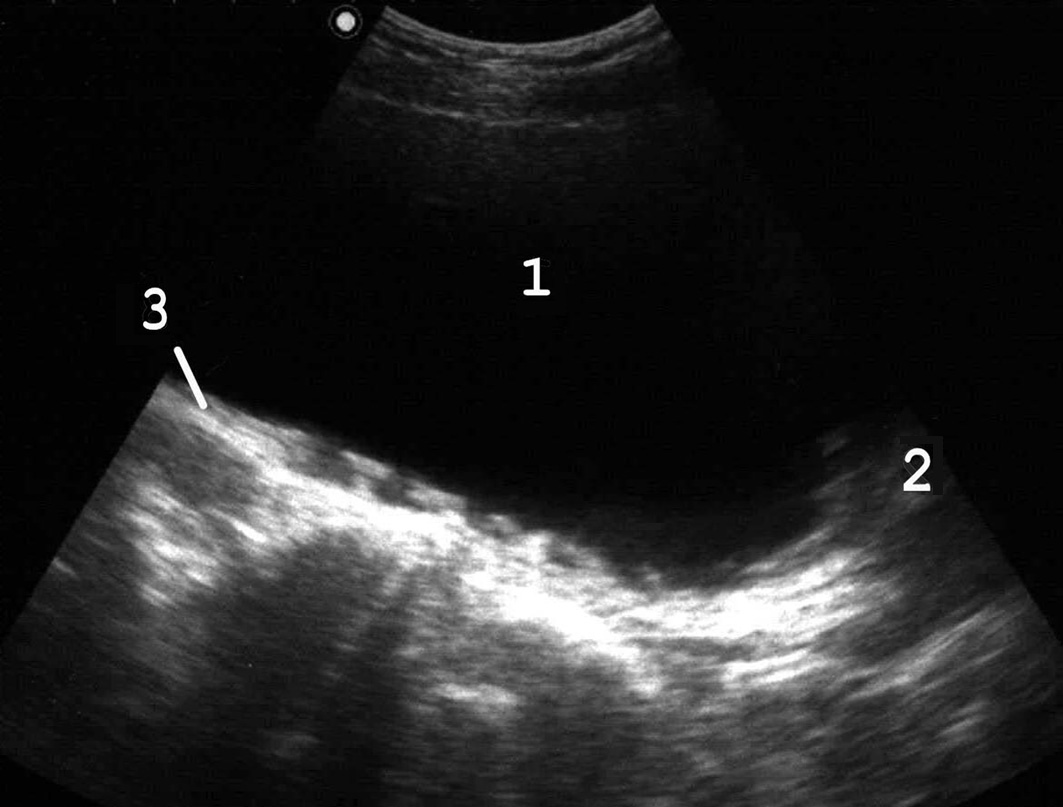

Рис. 7. В конечной стадии происходит перерастяжение стенок мочевого пузыря: 1 − мочевой пузырь; 2 − простата; 3 − истонченая трабекулярная стенка. (Продольное сканирование, конвексный датчик 5 МГц, “Logiq-500”).

Наиболее часто гипертрофия стенок связана с нарушением оттока мочи вследствие инфравезикальной обструкции. Ее причинами могут быть доброкачественная гиперплазия или рак предстательной железы, функциональный или органический стеноз шейки мочевого пузыря (болезнь Мариона), стриктура уретры. При прогрессировании заболевания и увеличении объема остаточной мочи утолщение мышечных пучков становится неравномерным, внутренняя поверхность мочевого пузыря принимает трабекулярный вид (рис. 6). Длительное существование хронической задержки мочи приводит к дальнейшему истончению стенок пузыря (рис. 7). Объем остаточной мочи может при этом достигать 1 л и более.